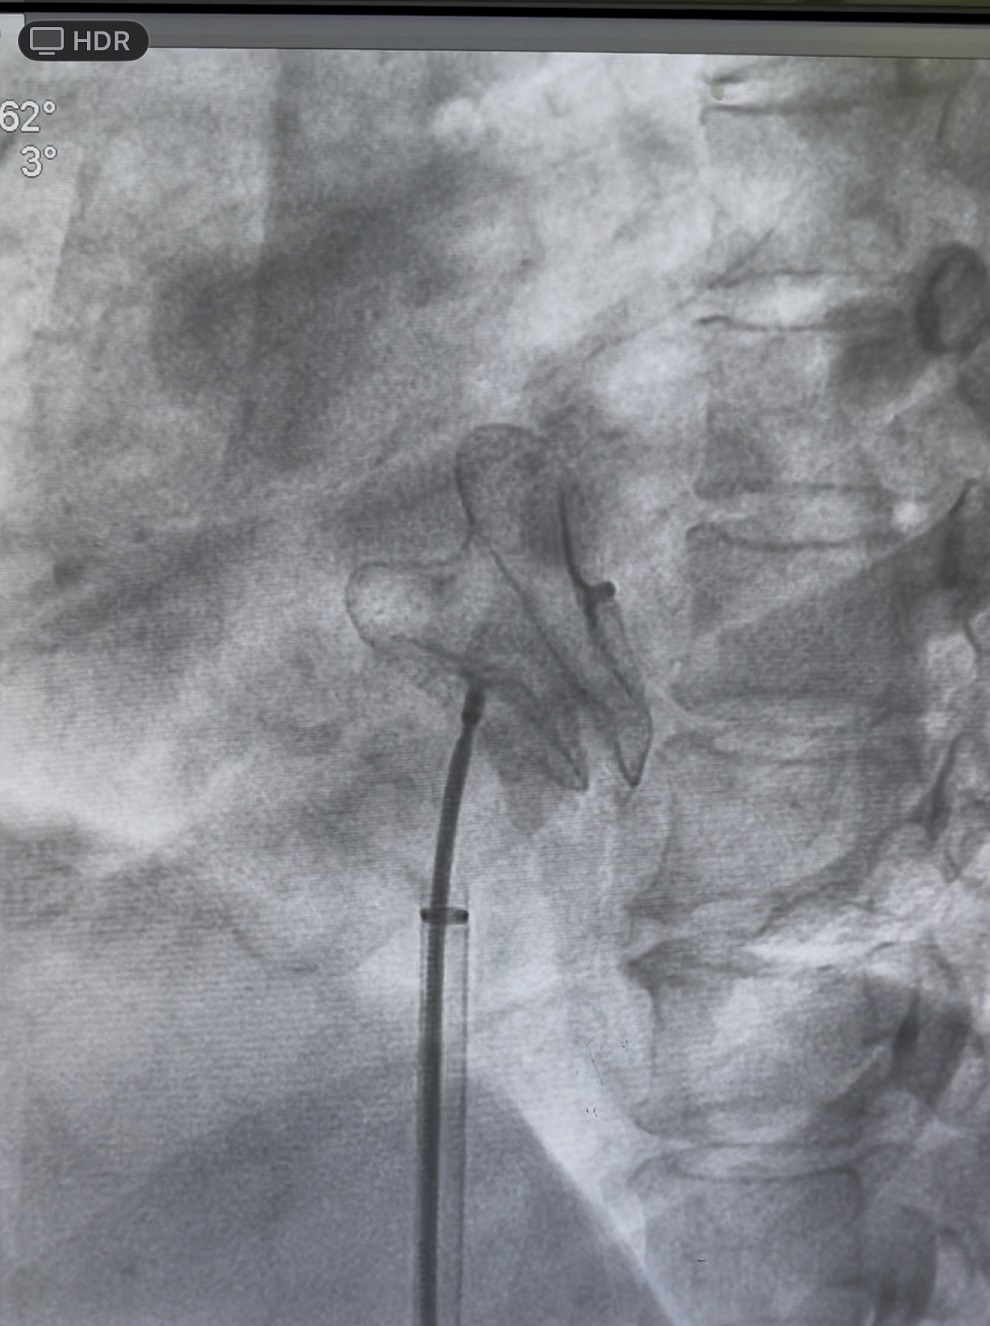

1. 病人72岁男患者,既往冠脉造影术中发生严重造影剂过敏导致休克,患者持续房颤20年病史,CHA2DS-VASC评分4分,HAS-BLED评分4分,左心耳封堵适应症强。常规左心耳封堵术需要再X线下做左心耳造影后,选择合适的封堵伞封堵。该病人术中无法使用造影剂。张晓君主任术前制定了周密手术方案,术前与我院心脏超声科经食道超声精确测量了左心耳各径线直径,术中张主任穿刺房间隔后在心腔内超声的引导下,选取27mm直径的左心耳封堵器成功封堵左心耳。术后患者恢复良好。该类零造影剂下的左心耳封堵术山东省为第四例,国内领先。